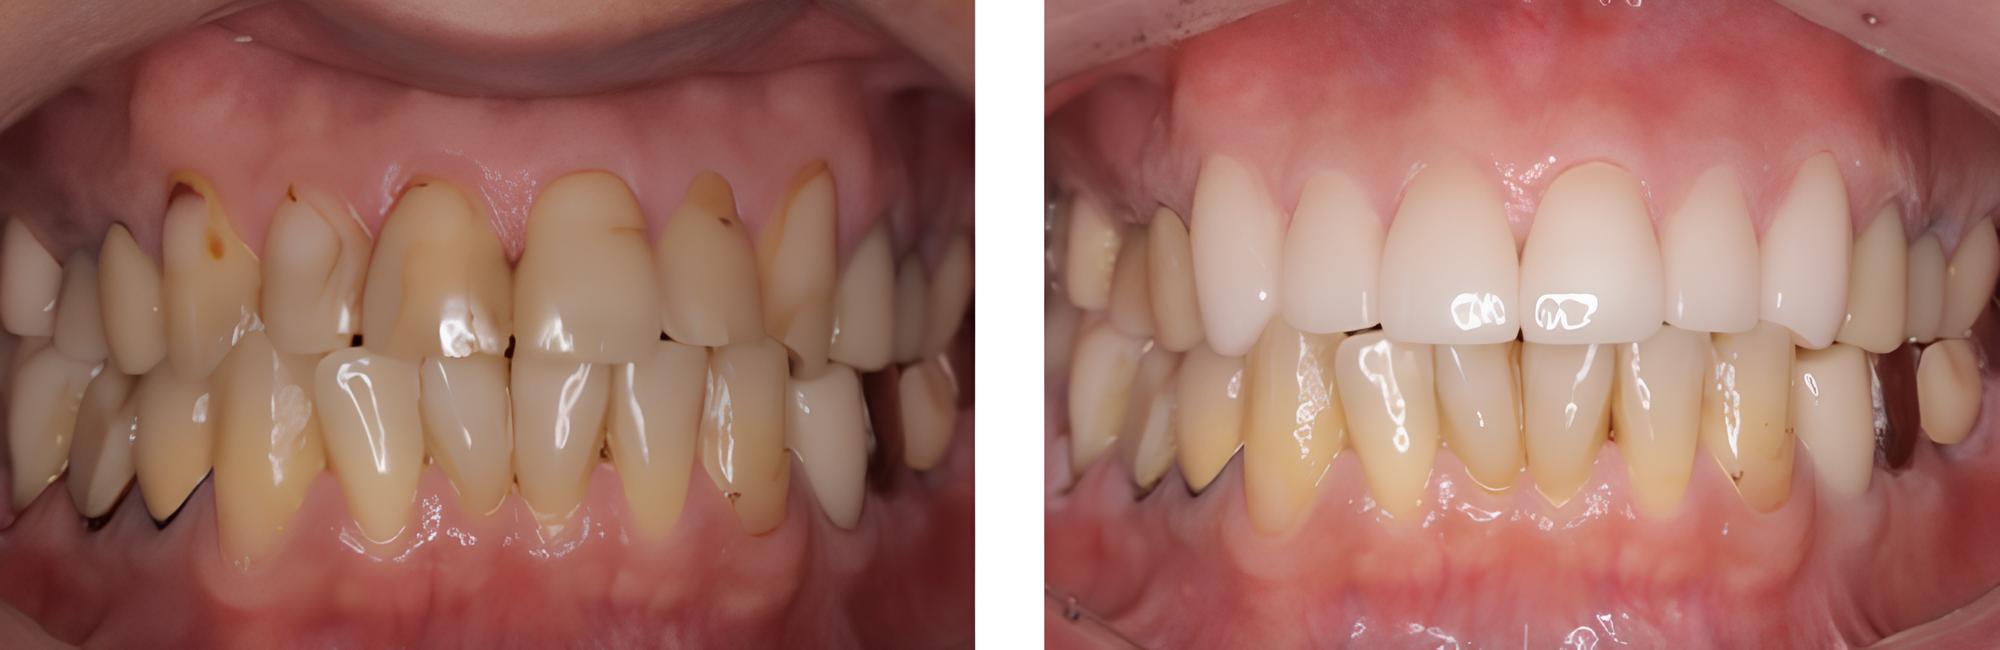

全顎保険治療

術前

術後

| 治療内容 | 全顎的に保険内で治療を行った |

|---|---|

| 治療期間・回数 | 約2.5年・約50回 |

| 費用 | 保険適用となります |